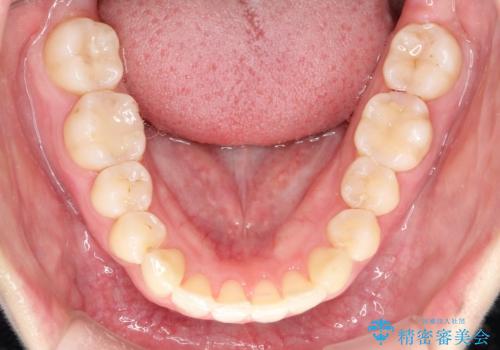

- 前歯の捻れと口元の突出を主訴に来院されました。

インビザラインを用いて上顎の遠心移動を行い、前歯を下げながら凸凹を綺麗に治すことができました。

歯を抜かない矯正治療を行う場合、口元は極端には変わりません。

今回は奥歯の遠心移動を行い、できる限り前歯を下げられるように治療を行いました。